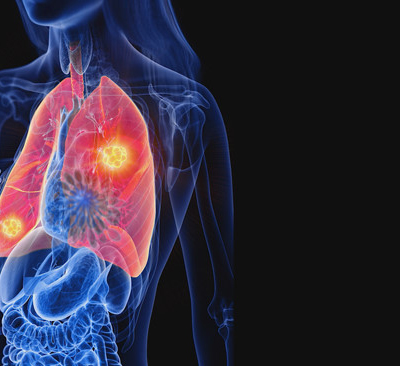

폐암 증상에는 기침, 체중 감소 흉통, 혈담 즉 피가 섞인 가래, 호흡곤란 등이 있지만, 위 증상은 다른 폐 질환에서도 나타날 수 있는 증상으로 구분하기가 어렵다. 그리고 폐암 초기에는 특별한 증상이 없는 경우가 대부분이라서 최근 흡연뿐 아니라 미세먼지 등 여러가지 요인으로 폐암이 발생하는 경우가 많아 정기검진으로 조기에 발견하는 것이 중요며 폐암 검진을 위해서는 특히나 저선량 흉부 CT를 촬영하는 것이 좋다라고 전문가들은 말하고 있습니다..